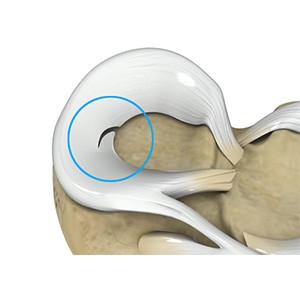

Picture of Meniscal Tears

Meniscal Tears

A meniscal tear is a common knee injury in athletes, especially those involved in contact sports. A sudden bend or twist in your knee causes the meniscus to tear. Elderly people are more prone to degenerative meniscal tears as the cartilage wears out and weakens with age.